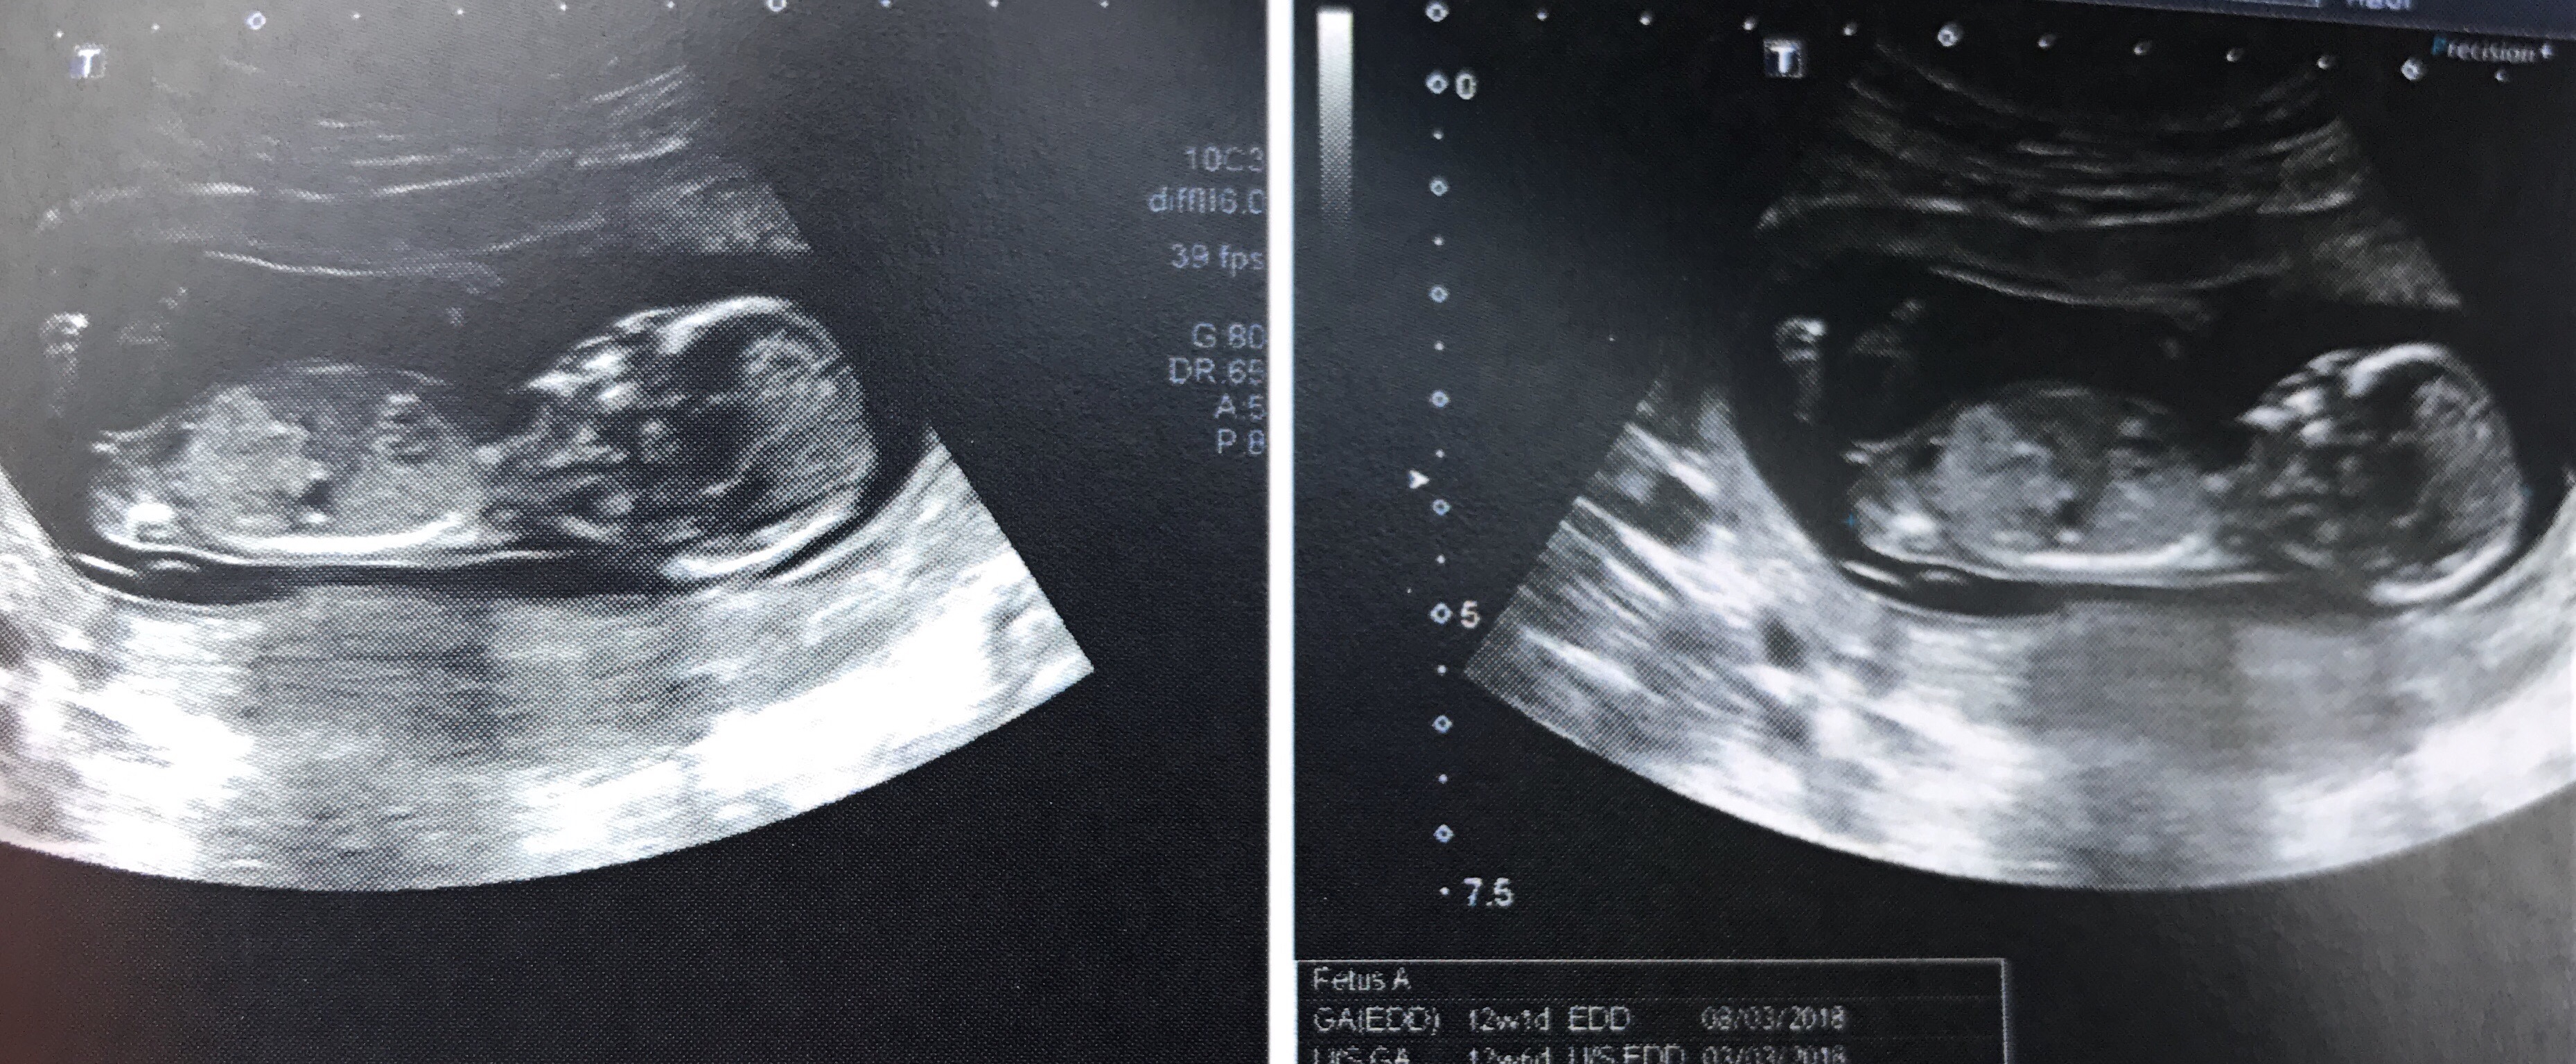

I'm 12+1 by my dating scan but 12+5 according to measurements in this scan.![]()

Nub Theory 12 week scan

I will be very shocked if that isn't a little girl x

Looking girly but there's potential for it to rise being only 12 weeks.

Confirmed girl at 20 weeks.